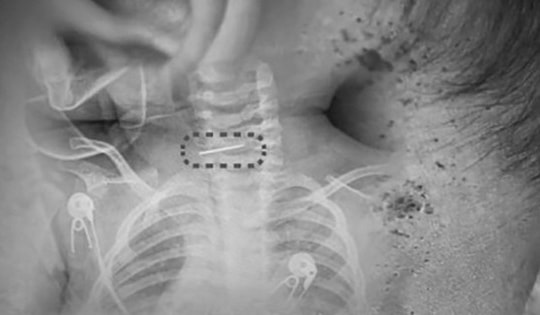

Co giật do sán làm tổ trong não

23/12/2025 14:44

Người đàn ông 39 tuổi bỗng xuất hiện đau đầu dữ dội, co giật, tưởng là u não, khi kiểm tra bác sĩ phát hiện ổ sán ký sinh.